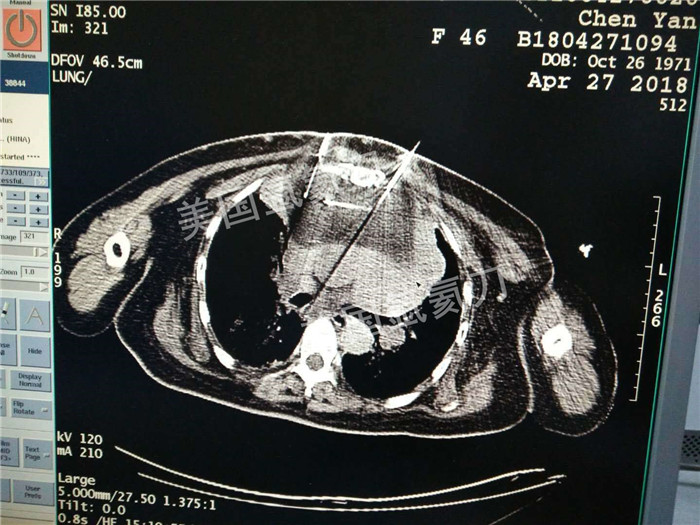

河北省中医院肿瘤科王利民主任胸腺19公分肿瘤氩氦刀手术

图片版权归美国氩氦刀所有,仅用于美国氩氦刀的宣传交流